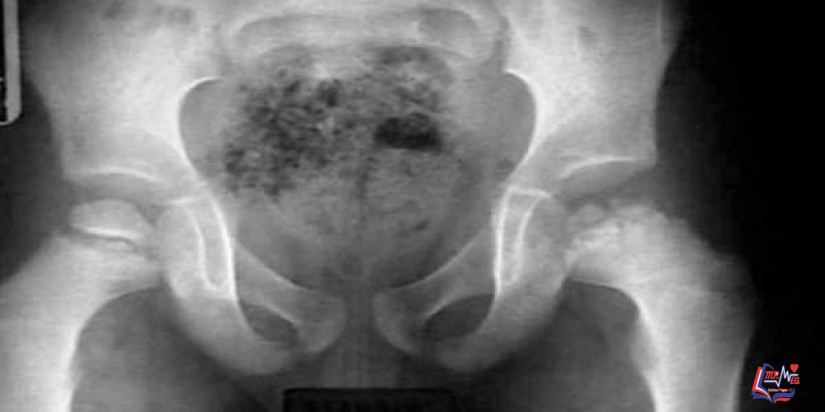

مرض بيرثيز Legg-Calve-Perthes disease

مرض بيرثيز أو متلازمة ليغ كالفيه بيرثيز، هو مرض يُصيب الأطفال عندما تُصبح رأس عظمة الفخذ الموجودة في مفصل الورك

المصدر Daily Medical Info اﻷمراض, أمراض الأطفال 2018-10-31 قراءة المزيد